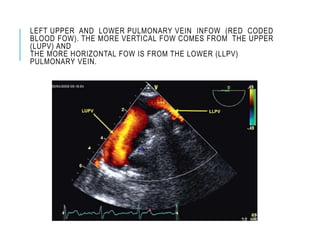

LEFT UPPER AND LOWER PULMONARY VEIN INFOW (RED CODED

BLOOD FOW). THE MORE VERTICAL FOW COMES FROM THE UPPER

(LUPV) AND

THE MORE HORIZONTAL FOW IS FROM THE LOWER (LLPV)

PULMONARY VEIN.